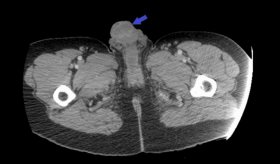

Según la experta, el virus previamente modificado, se inyecta directamente al tumor mediante una única intervención, y se espera la respuesta del paciente. Simultáneamente, en el Anderson Cancer Center se está llevando a cabo un estudio clínico que consiste en la aplicación del virus en células madre por la arteria de la muñeca.

"Los pacientes que estaban en el estudio clínico, son pacientes con el tumor más

maligno cerebral primario, que es el globlastoma, y tienen un pronóstico de vida recortado. Sin embargo, con la inyección de este virus, hubo un 20 % de pacientes que vivieron más de tres años, incluso cinco. Eran remisiones totales".